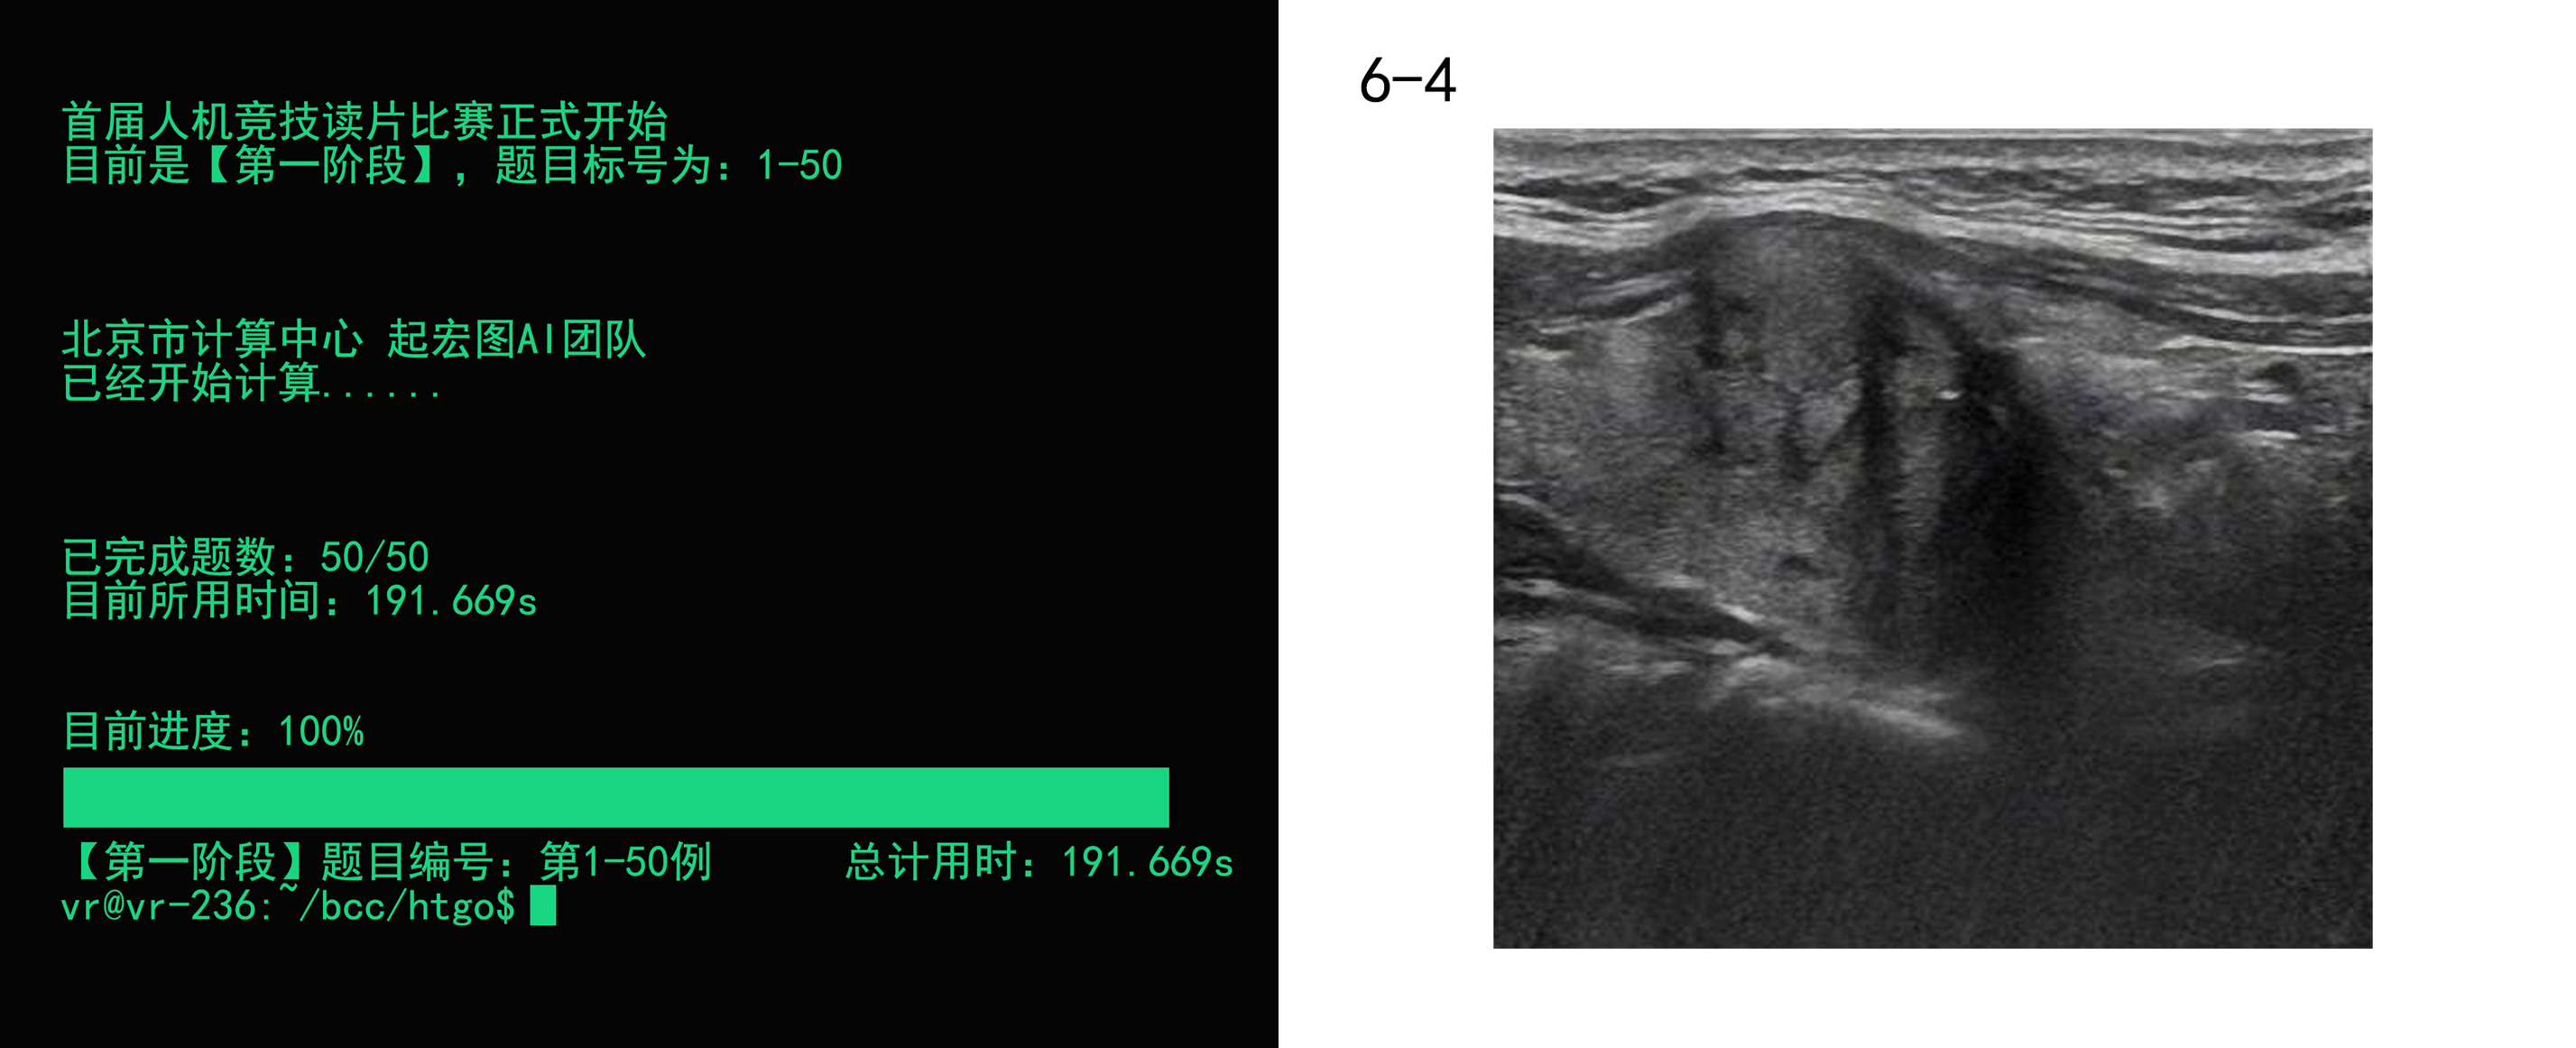

而AI的成绩是:191.669秒!

第一场部分答题结果:AI的正确率为68%,在与不同资历的医师相比,略高于高级医师的66%。

第二部分答题中,AI的准确率达到了76%左右,而大多数参赛医生的准确率均在60%-70%之间徘徊,仅有五名医生得分超过了AI。

最终成绩汇总,AI以73.0%的团队综合正确率取得第一名,领先第二名航天中心医院0.3%。